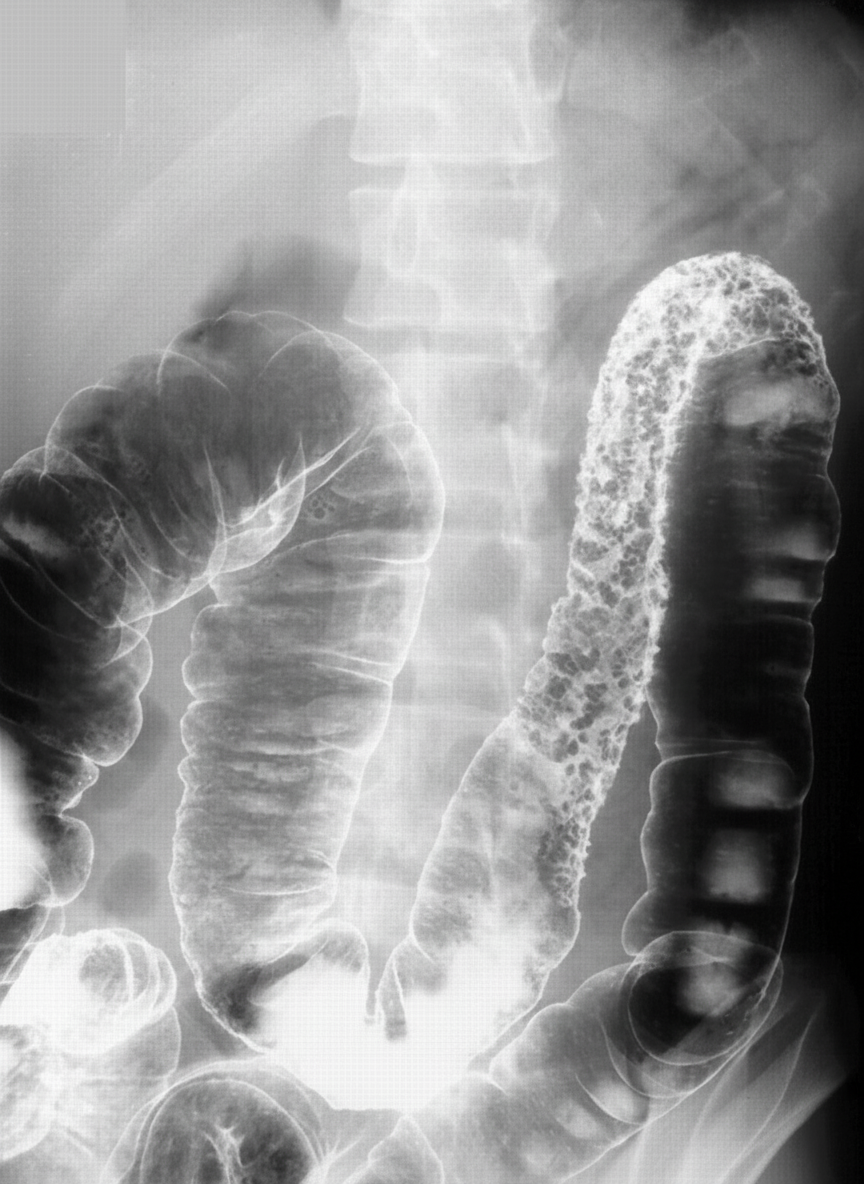

What is the diagnosis suggested by the barium study film?

Explanation: ***Crohn's disease*** - Barium studies show characteristic **string sign** (narrowed bowel segments), **skip lesions** (normal bowel between diseased areas), and **cobblestone mucosa** appearance. - **Rose-thorn ulcers** and **aphthous ulcers** create a distinctive pattern on barium enema, indicating transmural inflammation. *Toxic megacolon* - Barium studies show **massive colonic dilatation** (>6cm transverse colon) with **loss of haustral markings** and smooth colonic contour. - **Thumbprinting** may be present due to mucosal edema, but **skip lesions** and **string sign** are not characteristic features. *Intestinal perforation* - Barium studies would show **contrast extravasation** outside the bowel lumen into the **peritoneal cavity** or **retroperitoneum**. - **Free air** under the diaphragm or **pneumoperitoneum** may be visible, not the characteristic inflammatory changes of Crohn's disease. *Intussusception* - Barium enema demonstrates a **filling defect** with **coiled spring appearance** or **cup-shaped** obstruction at the intussusception site. - **Target sign** or **sausage-shaped mass** may be visible, but **transmural inflammation** and **skip lesions** are not present.